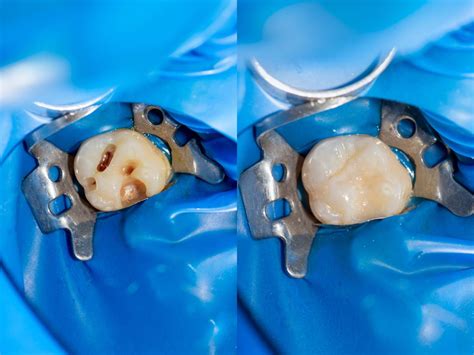

- Preparación del diente y eliminación de caries: Para continuar, con un taladro dental, se procede a la eliminación de las caries. Esto hará que queden unos pequeños agujeros o cavidades que deben limpiarse muy bien, para evitar que la infección pueda extenderse. Una vez que la anestesia ha hecho efecto, se procede a la eliminación de la caries. Con un instrumento dental especializado, el odontólogo retira el tejido afectado y cualquier resto de caries del diente. Tras limpiar la cavidad, se inicia el relleno con el material de obturación elegido, que puede ser composite, amalgama o porcelana.

- Aplicación del material de obturación: A continuación, se rellenan con material de obturación. El que se usa con mayor frecuencia en la actualidad es el composite o resina. Se aplica el material cuidadosamente, asegurándose de que se adapte perfectamente a la forma de la cavidad. Para aplicarla, el dentista agrega varias capas del material deteniéndose en cada una para endurecerla utilizando una lámpara de luz especial.

- Pulido y ajuste final: Una vez que haya rellenado por completo la cavidad, se pule la superficie y se aplica una prueba de mordida. Este paso es fundamental para que la restauración se integre de manera natural con el diente adyacente. De esta forma le puedes indicar al dentista si el relleno quedó muy elevado y te genera molestias al morder. Después de la obturación, es importante seguir una serie de cuidados para asegurar la durabilidad del tratamiento.